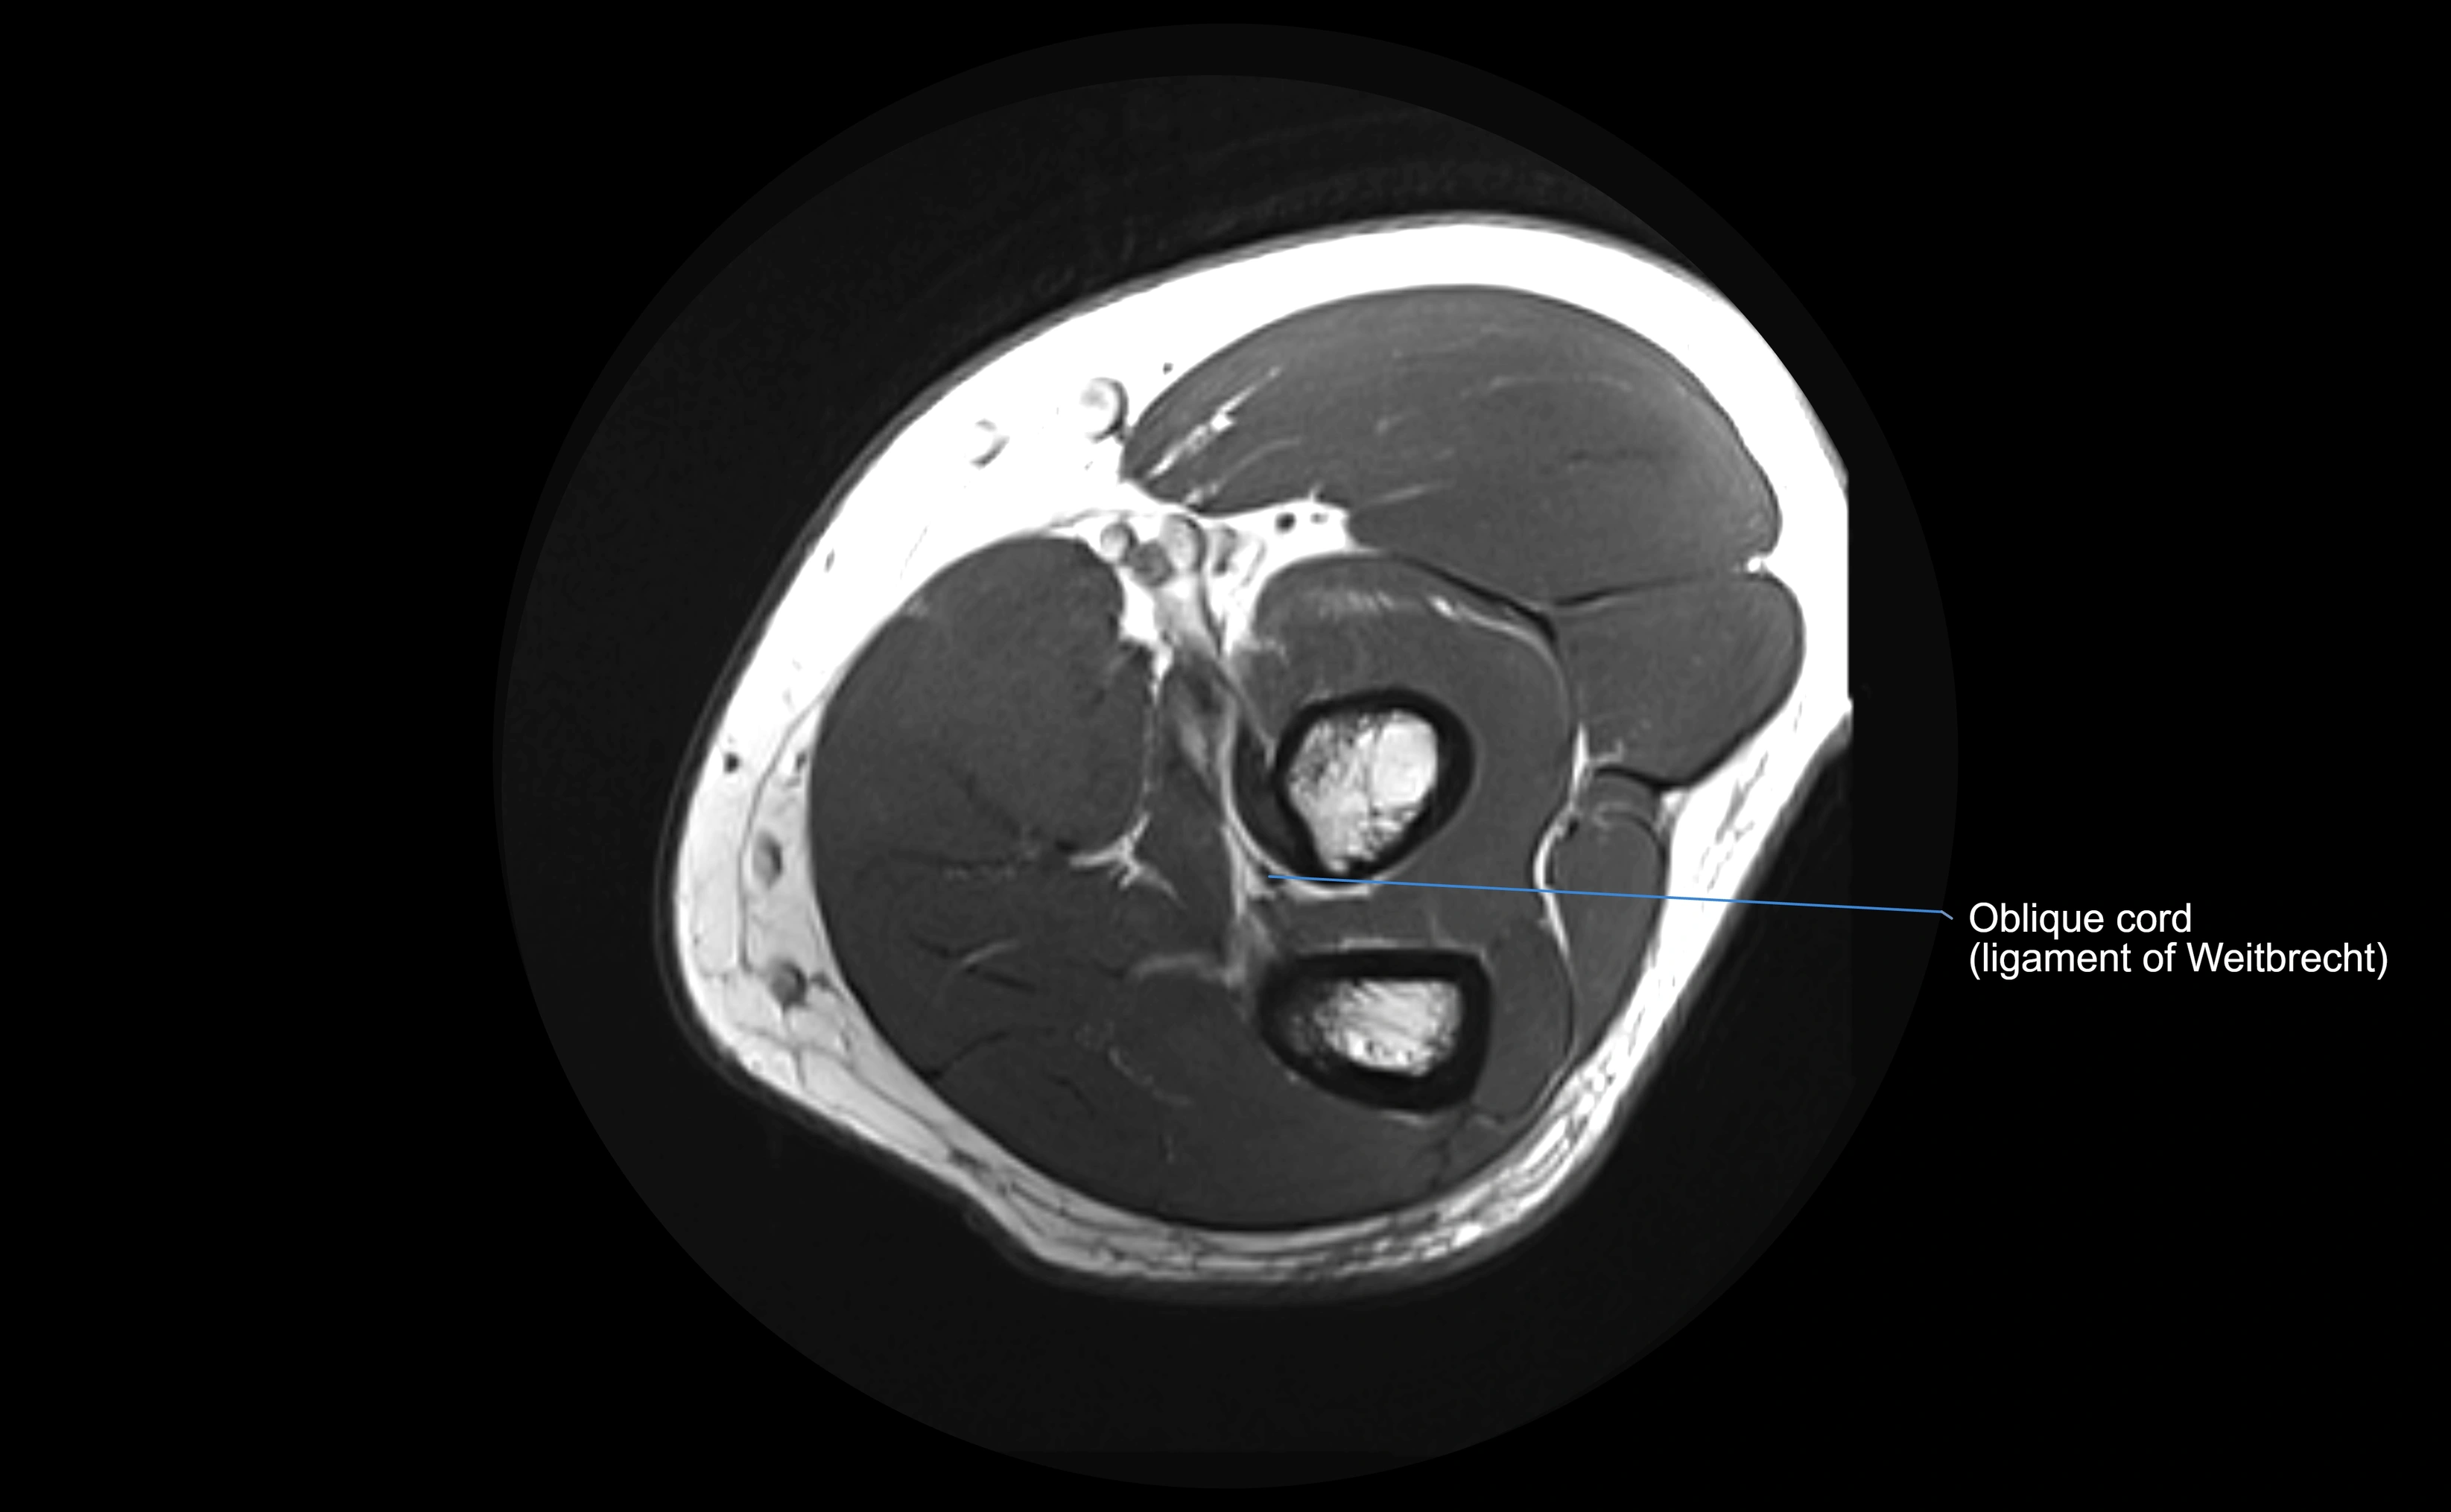

Origin, Course, and Insertion

• Origin: Arises from the anterior margin of the radial notch of the ulna.

• Course: Forms a strong circular band that wraps around the radial head and neck, maintaining them within the radial notch.

• Insertion: Attaches to the posterior margin of the radial notch, completing a fibrous ring around the radial head.

• The inner surface of the ligament is lined with synovial membrane, allowing frictionless rotation.

Relations

• Superiorly: Blends with the capsule of the elbow joint.

• Inferiorly: Supported by the quadrate ligament at the neck of the radius.

• Medially: Attached to the ulnar radial notch.

• Laterally: In contact with the radial head and its articular cartilage.

• Anteriorly: Related to the radial collateral ligament of the elbow.

• Posteriorly: Continuous with the elbow joint capsule.